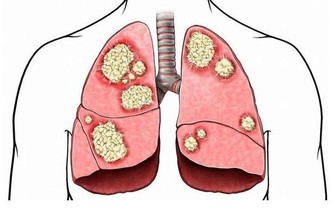

在夏天的悶熱過後,很快就迎來了秋天的涼爽與乾燥,老百姓都知道秋天是比較乾燥的季節,這個時期,對於鼻子粘膜比較薄的人會出現鼻出血的情況,對於肺臟本身不是很好的人,容易在這個時期出現咳嗽的表現,這些其實都是秋燥傷害了人體正常的陰液分佈,導致的結果。

通常情況下,體內有濕的患者就不適宜潤秋燥,因為體內的濕邪不去,然後又用很滋膩的食物進行補養,所以對於身體來說是更加的不利,更加不利於體內濕氣的祛除,就會使疾病更加加重。